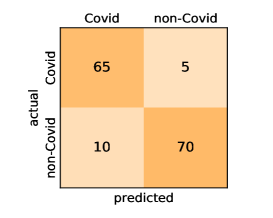

Here, we present and discuss the obtained results for detecting COVID-19 on the considered CT image datasets with different deep networks. We report the quantitative results along with the confusion matrices for every single architecture of the adopted networks.

On the SARS-CoV-2 CT dataset, ResNet101 achieves the best overall performance with respect to almost all evaluation metrics, with an average accuracy and F1-score of and , respectively. The model also achieves an average sensitivity rate of indicating that, on average, only two COVID-19 images are falsely predicted as negatives. It is also powerful enough to correctly identify all Non-COVID-19 cases with only one false positive resulting a specificity rate of . The highest sensitivity score of is achieved by the InceptionV3 model, where only one COVID-19 image is falsely predicted as negative on average. The SqueezeNet model obtains the lowest performance with respect to all evaluation metrics with a fairly acceptable average accuracy and sensitivity scores of and , respectively. Also the ShuffleNet architecture obtains satisfactory performance with approximately improvements on average for all metrics compared with SqueezeNet. Although the results obtained by these models are inferior compared with the rest of models, but they are more efficient. This matches their main objective of reducing the computational costs rather than improving their visual recognition abilities. The rest of models achieve competitive performance and very promising results with slight performance differences. Comparing the different variants of ResNet and DenseNet, we can see that the deeper variants from each architecture yield a slightly better performance. The deeper ResNet101 and ResNeXt101 show a marginal gain in performance compared with their shallower counterparts. The details about class-wise results for each model are summarized in the confusion matrices in Figure 9.